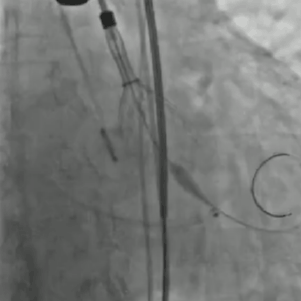

从三叶瓣重度钙化到二叶瓣畸形的根部解剖,从单纯主动脉瓣反流到入路极端迂曲挑战的案例。TaurusOne凭借其优异的柔顺性,支撑力强及内外层双侧裙边的特点,都能从容应对复杂的临床患者解剖结构。从患者的临床选择到术后的长久获益,从手术入路的种类到术中操作的注意事项,从围术期卒中的循证医学到术后的抗凝抗栓用药规范,在线专家共同交流彼此中心的围术期TAVR经验和分享现阶段经导管主动脉瓣置换的诊疗策略。针对当前TAVR领域多个热点学术问题进行了热烈的讨论,现场可谓精彩纷呈、高潮迭起。专家们纷纷借此契机相互交流探讨,分享各自的单中心经验,力求进一步提升TAVR手术的安全性和有效性,为主动脉瓣相关疾病的患者带来长远综合获益。